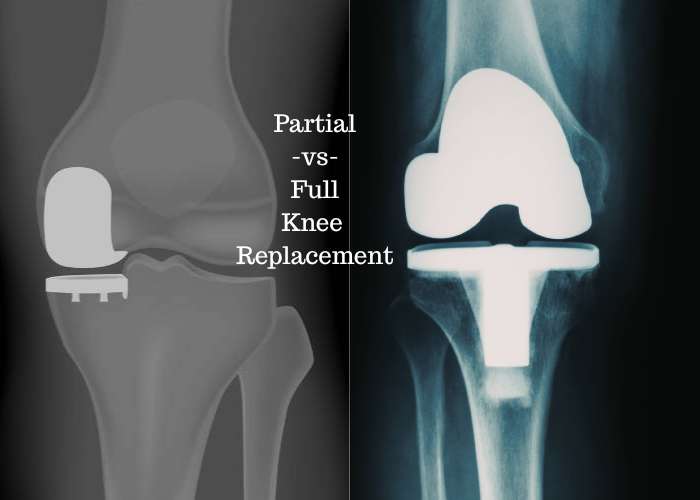

Dr. Prem N. Ramkumar, MD, MBA, is a dual fellowship trained, board-certified orthopaedic surgeon with focused expertise in hip and knee conditions, from Sports Medicine/Arthroscopy to Joint Replacement/Adult Reconstruction. Dr. Ramkumar treats patients at Long Beach Lakewood Orthopedic Institute within the Commons Clinic network serving Orange County, Los Angeles, Long Beach and surrounding Southern California areas. He received his medical education and surgical training at Cleveland Clinic, Harvard/Brigham and Women's Hospital, and Hospital for Special Surgery – the #1 ranked orthopaedic hospital in the country. He was privileged to serve as Assistant Team Physician to the NBA's Brooklyn Nets and MLS' Red Bulls during his time at Hospital for Special Surgery. With over 140 peer-reviewed publications, 11 textbook chapters, published 10 articles in Forbes (among other circulations), Dr. Ramkumar lectures nationally and internationally and serves as the Associate Editor for Digital and Emerging Technologies for Arthroscopy, the Journal for Arthroscopic and Related Surgery. He has also been appointed Associate Editor for The Journal of Bone and Joint Surgery (JBJS) for Adult Reconstruction (Knee).